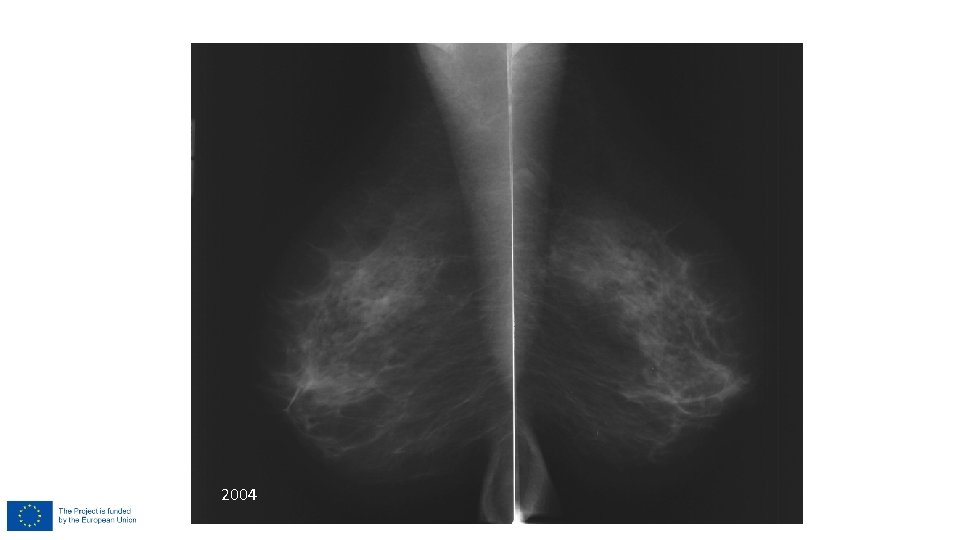

PHT 2004

Density

Density 3 -4 Dense breast – higher breast cancer risk! • Inform women about low sensitivity of MG in dense breasts • Use digital MG • Ultrasound in screening ? • Ultrasound as further recommendation